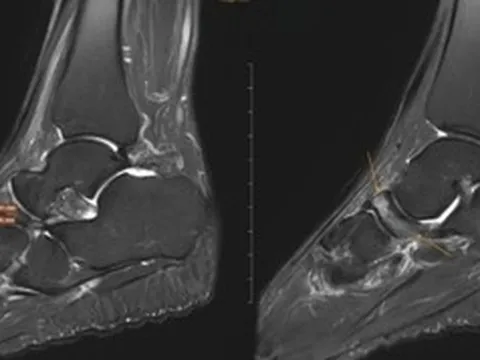

Ngay sau đó, các bác sĩ đã nhanh chóng tiến hành chụp cắt lớp vi tính bụng, tiểu khung, lồng ngực, sọ não và thực hiện các xét nghiệm cận lâm sàng, hội chẩn các chuyên khoa Cấp cứu, Hồi sức tích cực – chống độc, Khoa Ngoại nhi.

Kết quả chẩn đoán cho thấy, trẻ bị suy hô hấp độ 3, sốc chấn thương, đa chấn thương. Bé gái còn bị chấn thương ngực kín, gãy xương sườn bên trái, đụng dập nhu mô, tràn khí – tràn máu màng phổi hai bên, chấn thương bụng kín, chấn thương gan độ 3, chấn thương lách độ 3.